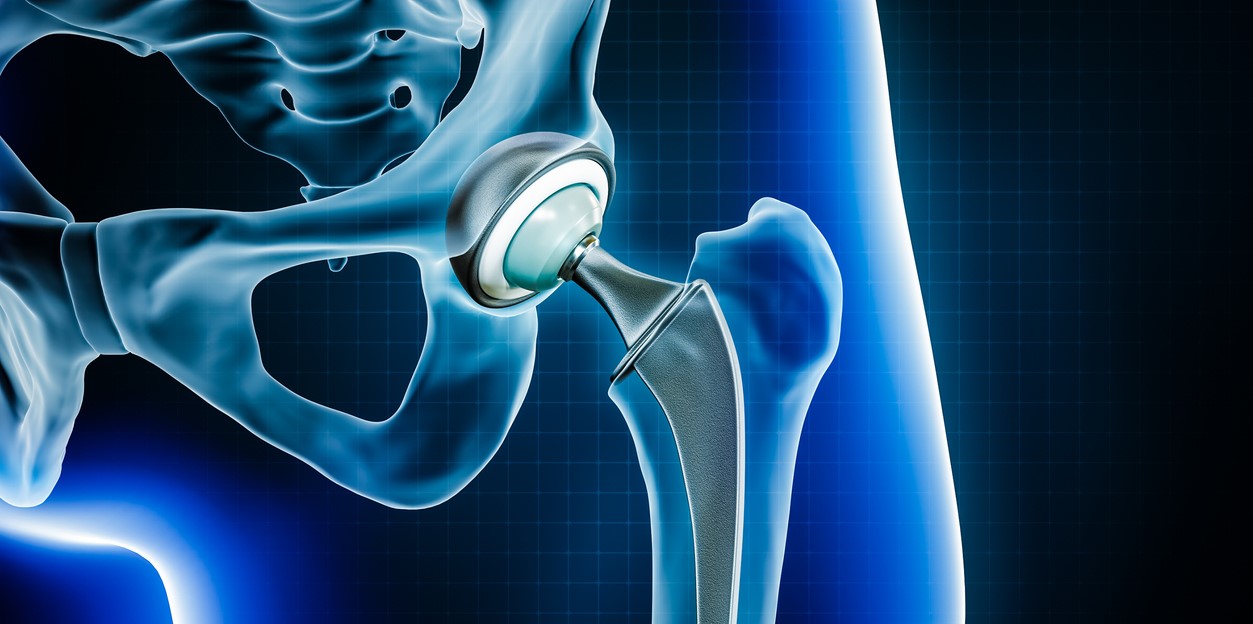

Hip replacement involves removing the damaged parts of the hip joint and replacing them with artificial components made of metal, ceramic, or high-grade plastic. The goal of the surgery is to reduce pain, improve joint function, and enhance mobility. There are two main types of hip replacement:

1.Total Hip Replacement (THR): The entire hip joint (femoral head and socket) is replaced.

2.Partial Hip Replacement: Only the femoral head is replaced, often used for certain types of fractures.

Hip replacements can also be done using cemented or uncemented implants, depending on the patient’s age, bone quality, and activity level. Orthopedic & Joint Replacement Treatment in India.